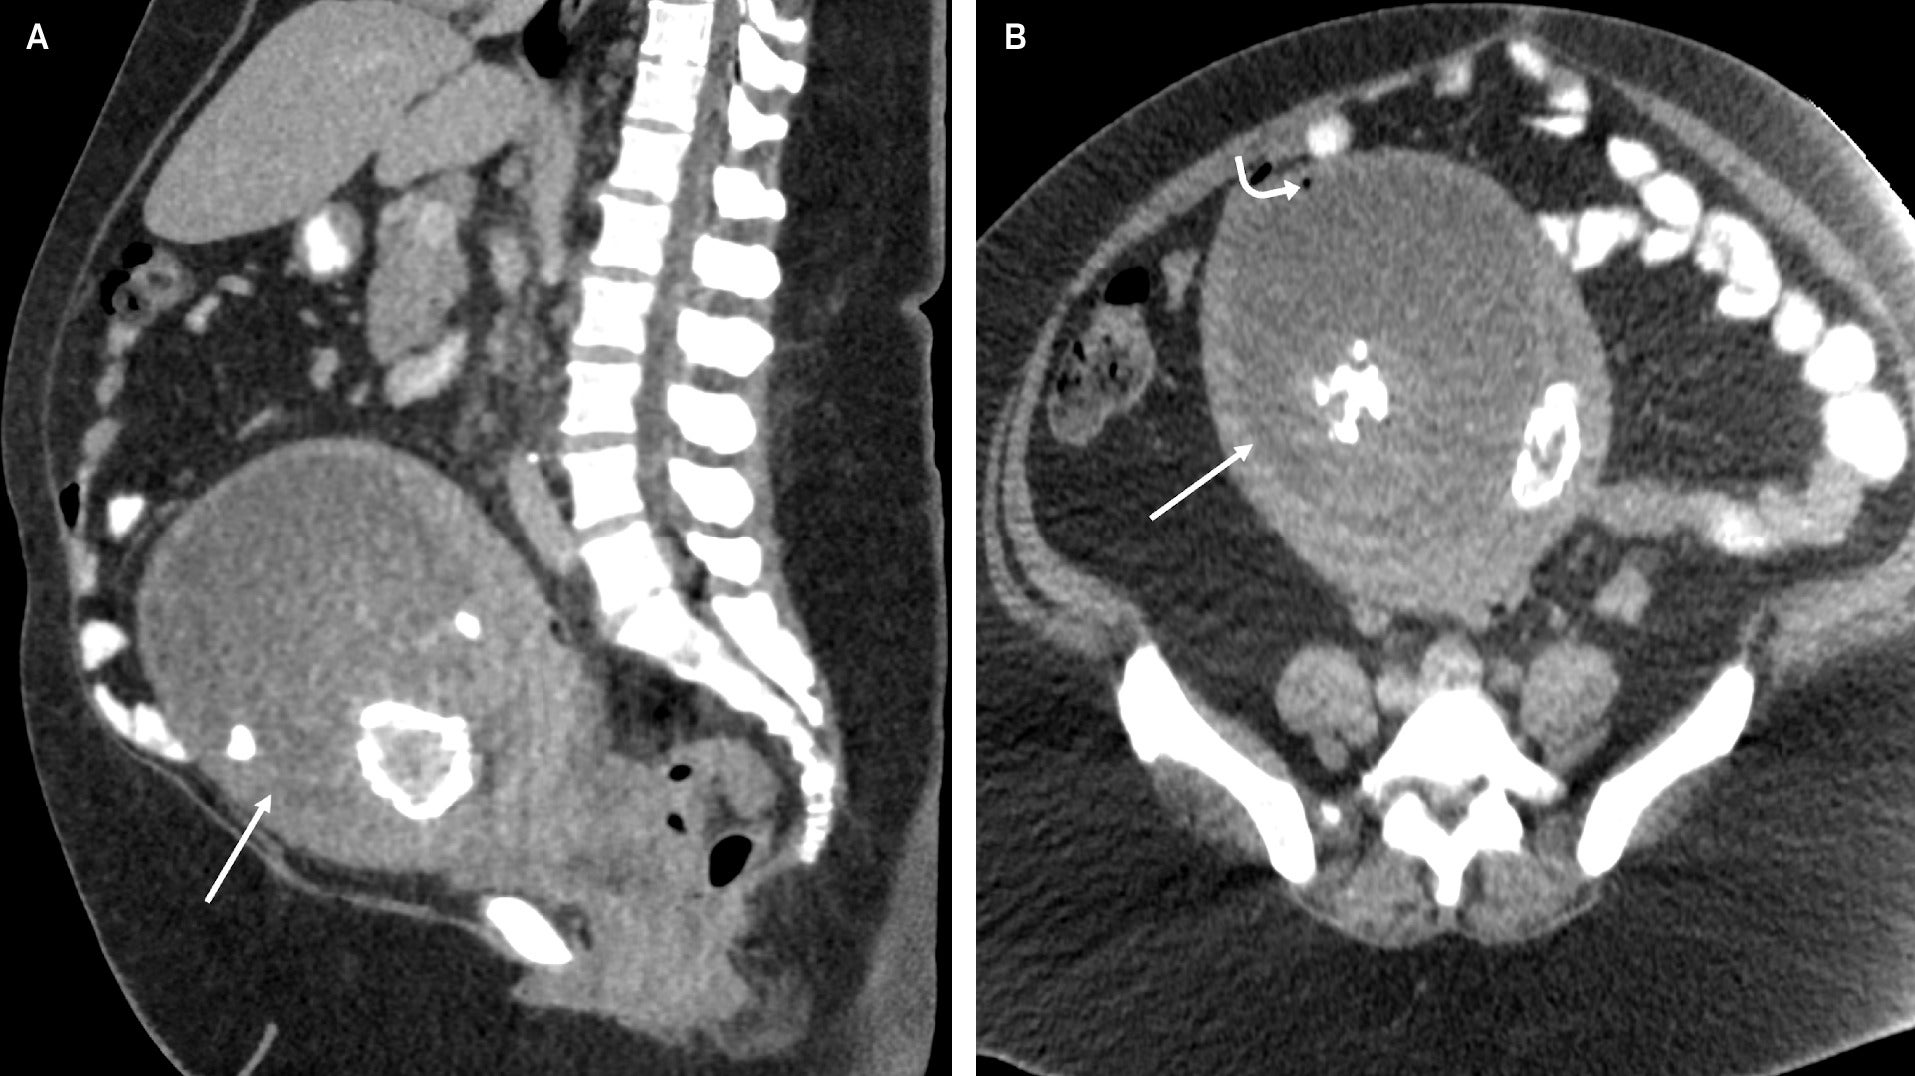

Abdominopelvic CT with intravenous contrast performed upon initial presentation showed a lobular enlarged uterus with a centrally necrotic, partially calcified intramural uterine fibroid at the uterine fundus, which contained a small locule of gas along the anterior myometrial mantle ( Figure 1 ). A subsequent MRI of the pelvis was performed without intravenous contrast and demonstrated similar findings ( Figure 2 ).

Sagittal (A) and axial (B) CT of the abdomen and pelvis after the administration of intravenous contrast shows an enlarged uterus with a centrally necrotic and partially calcified myometrial mass (straight arrow). There is a single locule of air within the necrotic portion of the fibroid anteriorly (curved arrow).